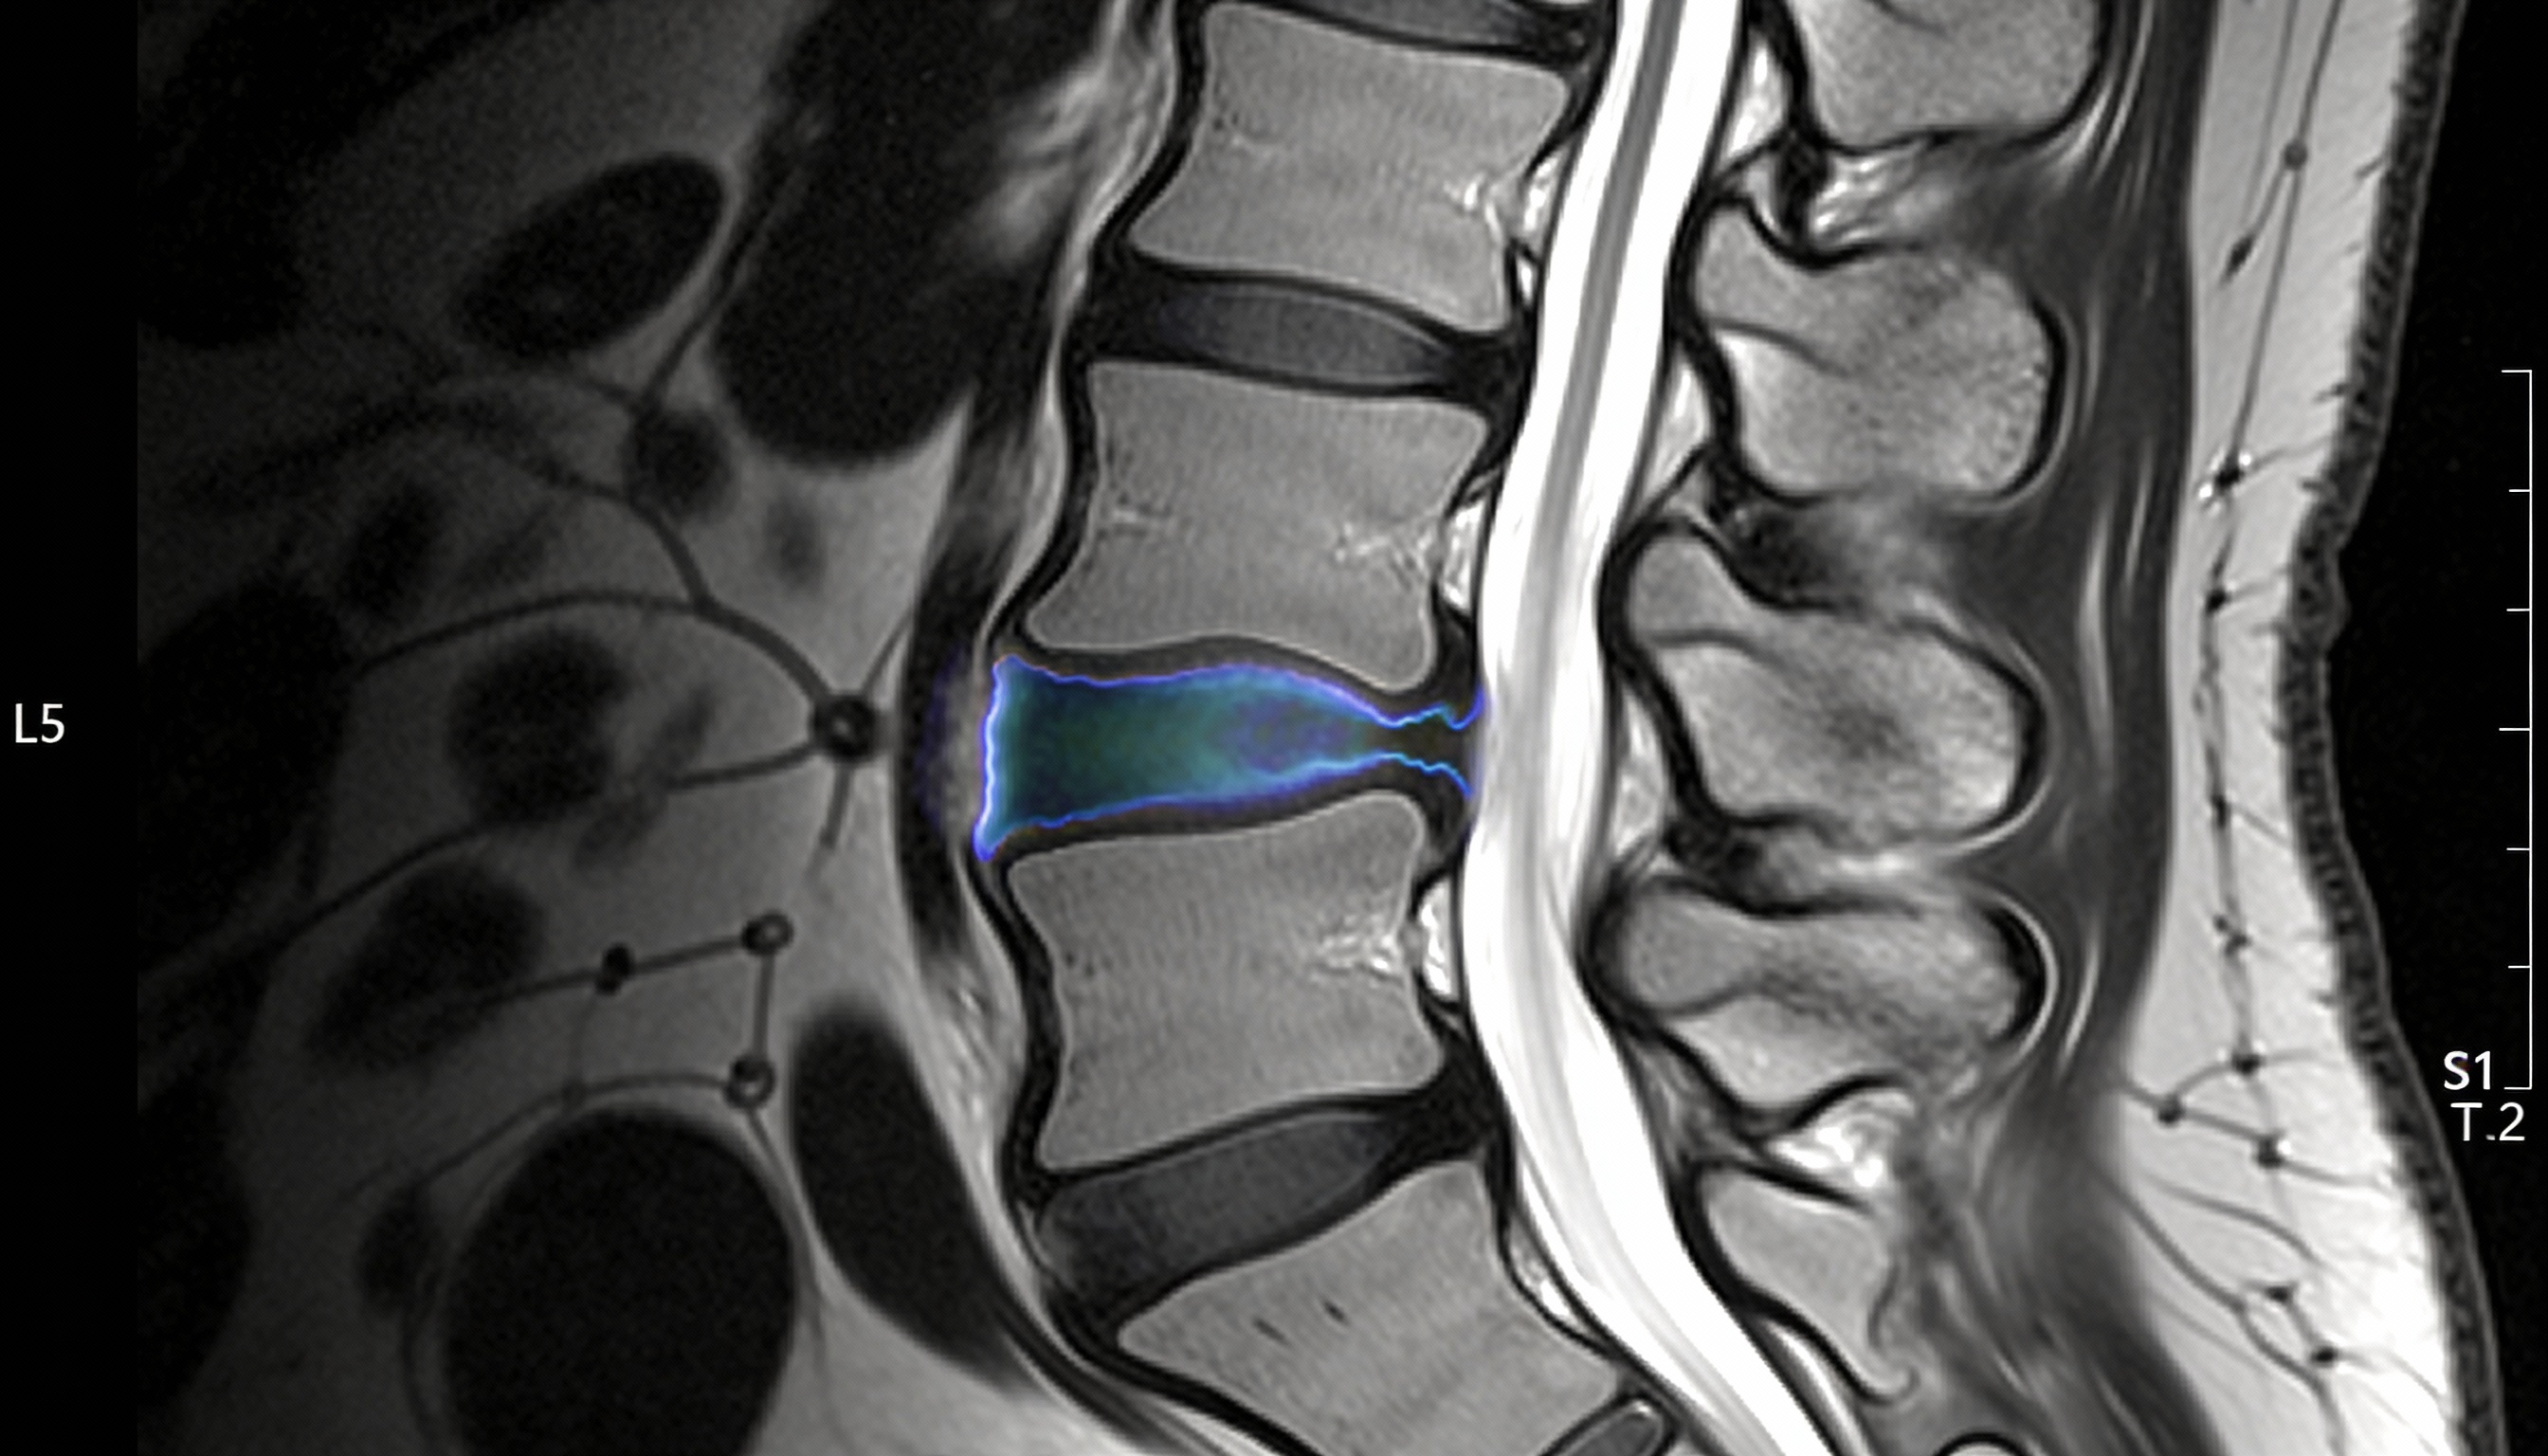

Para evitar cirugías innecesarias, acceder a técnicas de mínima invasión y confirmar si el hallazgo de la resonancia tiene realmente relevancia clínica.

Microdiscectomía o endoscopía para eliminar la ciática refractaria con un 95% de éxito comprobado.